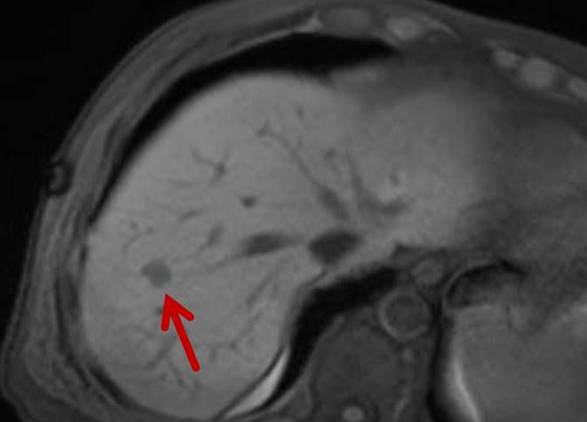

Die minimalinvasive Thermoablation ist eine Therapieoption für Leberkarzinome und Lebermetastasen. Voraussetzung hierfür ist, dass bestimmte Bedingungen wie Tumorgröße, Anzahl und Lage des Zieltumors erfüllt sein. Ob ein Lebertumor mit einem thermoablativen Verfahren (Mikrowellenablation oder Radiofrequenzablation) sicher und effektiv behandelt werden kann, wird vor der Therapie interdisziplinär mit Kollegen aller für diese Fragestellung relevanter Fachrichtungen besprochen.

Abbildung: Bei diesem Patienten wurde ein im Röntgen nur schlecht sichtbarer Knochentumor vor der Operation unter MRT-Kontrolle mit kleinen röntgendichten Spiralen („Coils“) markiert. Damit hat der Operateur eine optimale Darstellung des Tumorbereichs bzw. der Tumorgrenzen und kann gezielter, schonender und effektiver operieren.